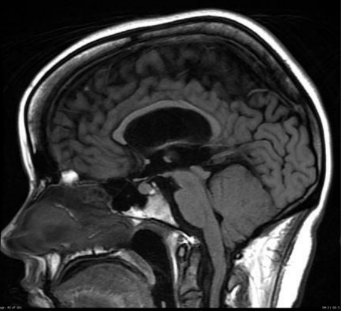

Q

What is this?

A

Communicating hydrocephalus at the level of lateral ventricle